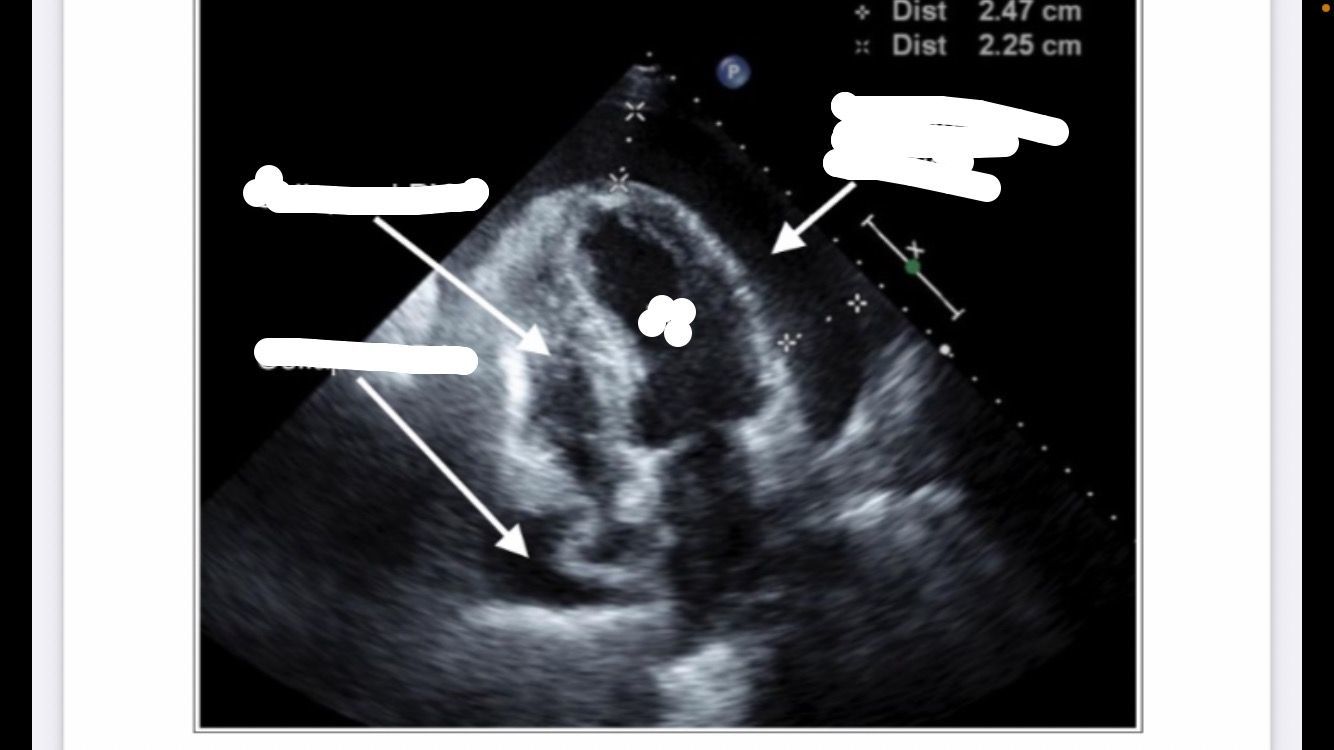

TTE IMAGE OF TAMPONADE